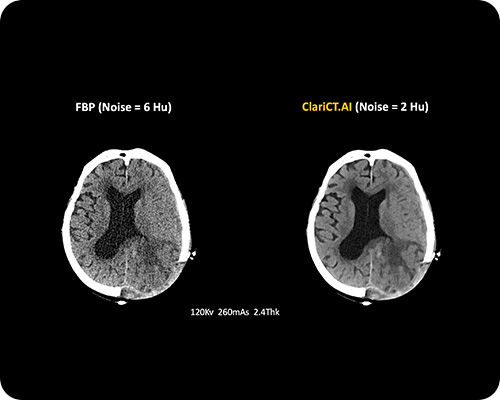

ClariCT.AI

AI-Powered Radiation Reduction

The first AI software that dramatically reduces radiation exposure while delivering the highest quality CT images using advanced AI denoising technology.

Reduces radiation exposure by 70-95% while maintaining superior image quality